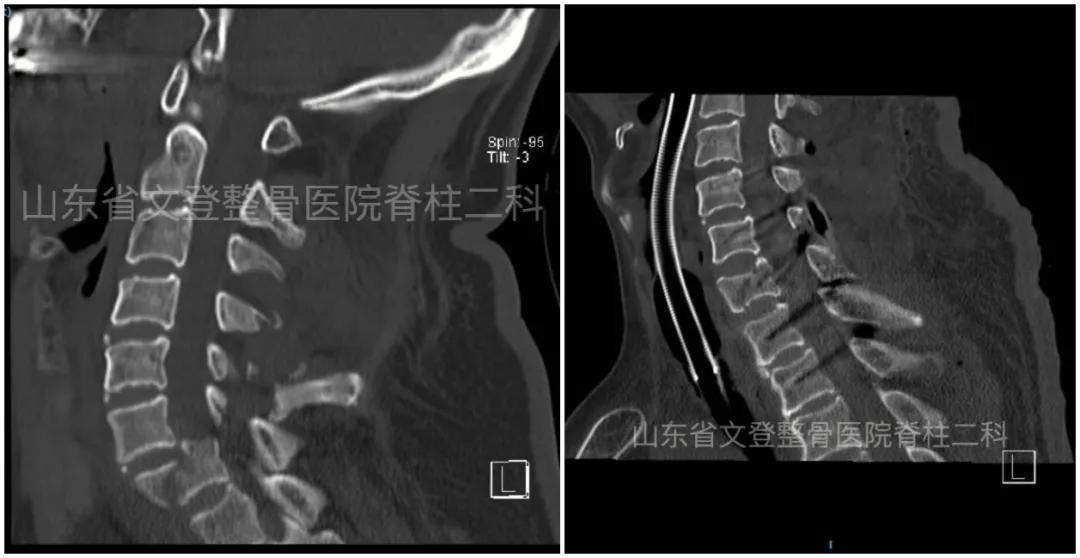

术前颈椎CT(矢状位)

术前颈椎MRI(矢状位) 术前胸椎CT(矢状位)